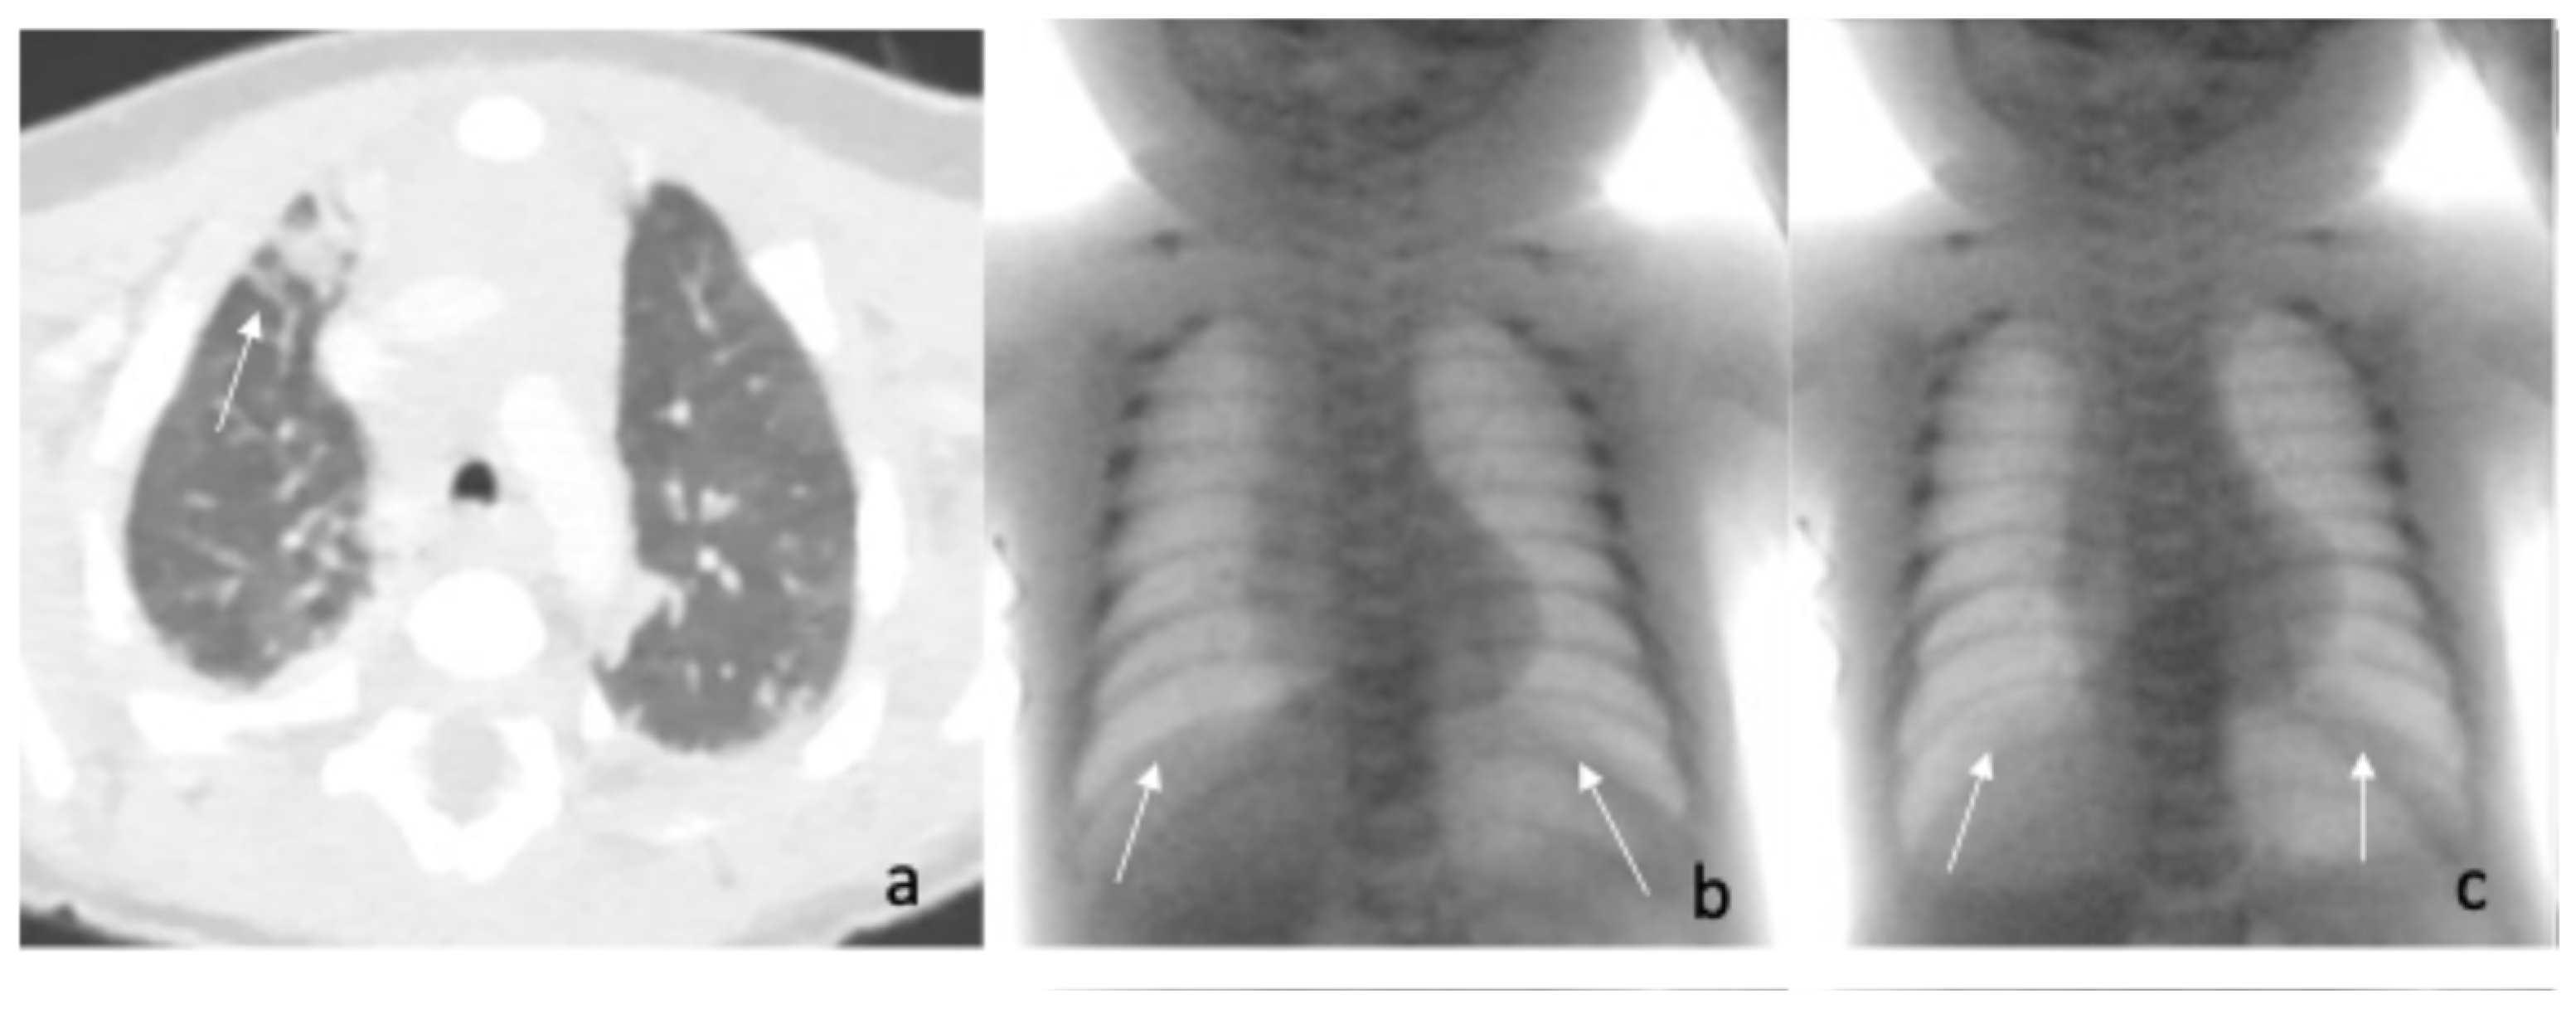

| Fluoroscopic evaluation | Inadequate bilateral diaphragm excursion | Reduced diaphragmatic excursion |

| Treatment | Bilateral diaphragmatic plication at 45 days of age | Tracheostomy at 2 months of life |